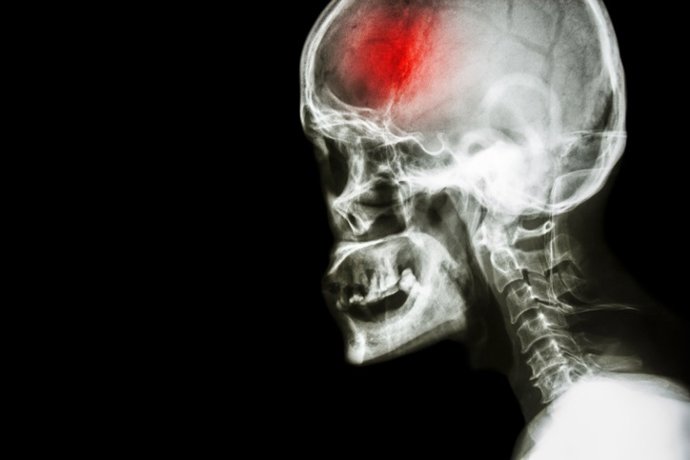

Archivo - Cerebro, epilepsia, ictus

Archivo - Cerebro, epilepsia, ictus - GETTY IMAGES/ISTOCKPHOTO / STOCKDEVIL - Archivo

Cuando se produce un ictus hemorrágico, cada minuto cuenta. El sangrado dentro del cerebro avanza rápido y las opciones terapéuticas siguen siendo muy limitadas, lo que convierte este tipo de accidente cerebrovascular en uno de los más letales.

Una hemorragia intracerebral (HIC) se produce cuando un vaso sanguíneo se rompe dentro del cerebro y causa una hemorragia cerebral. Las HIC representan aproximadamente el 15% de todos los accidentes cerebrovasculares, pero un desproporcionado 50% de todas las muertes por accidente cerebrovascular.